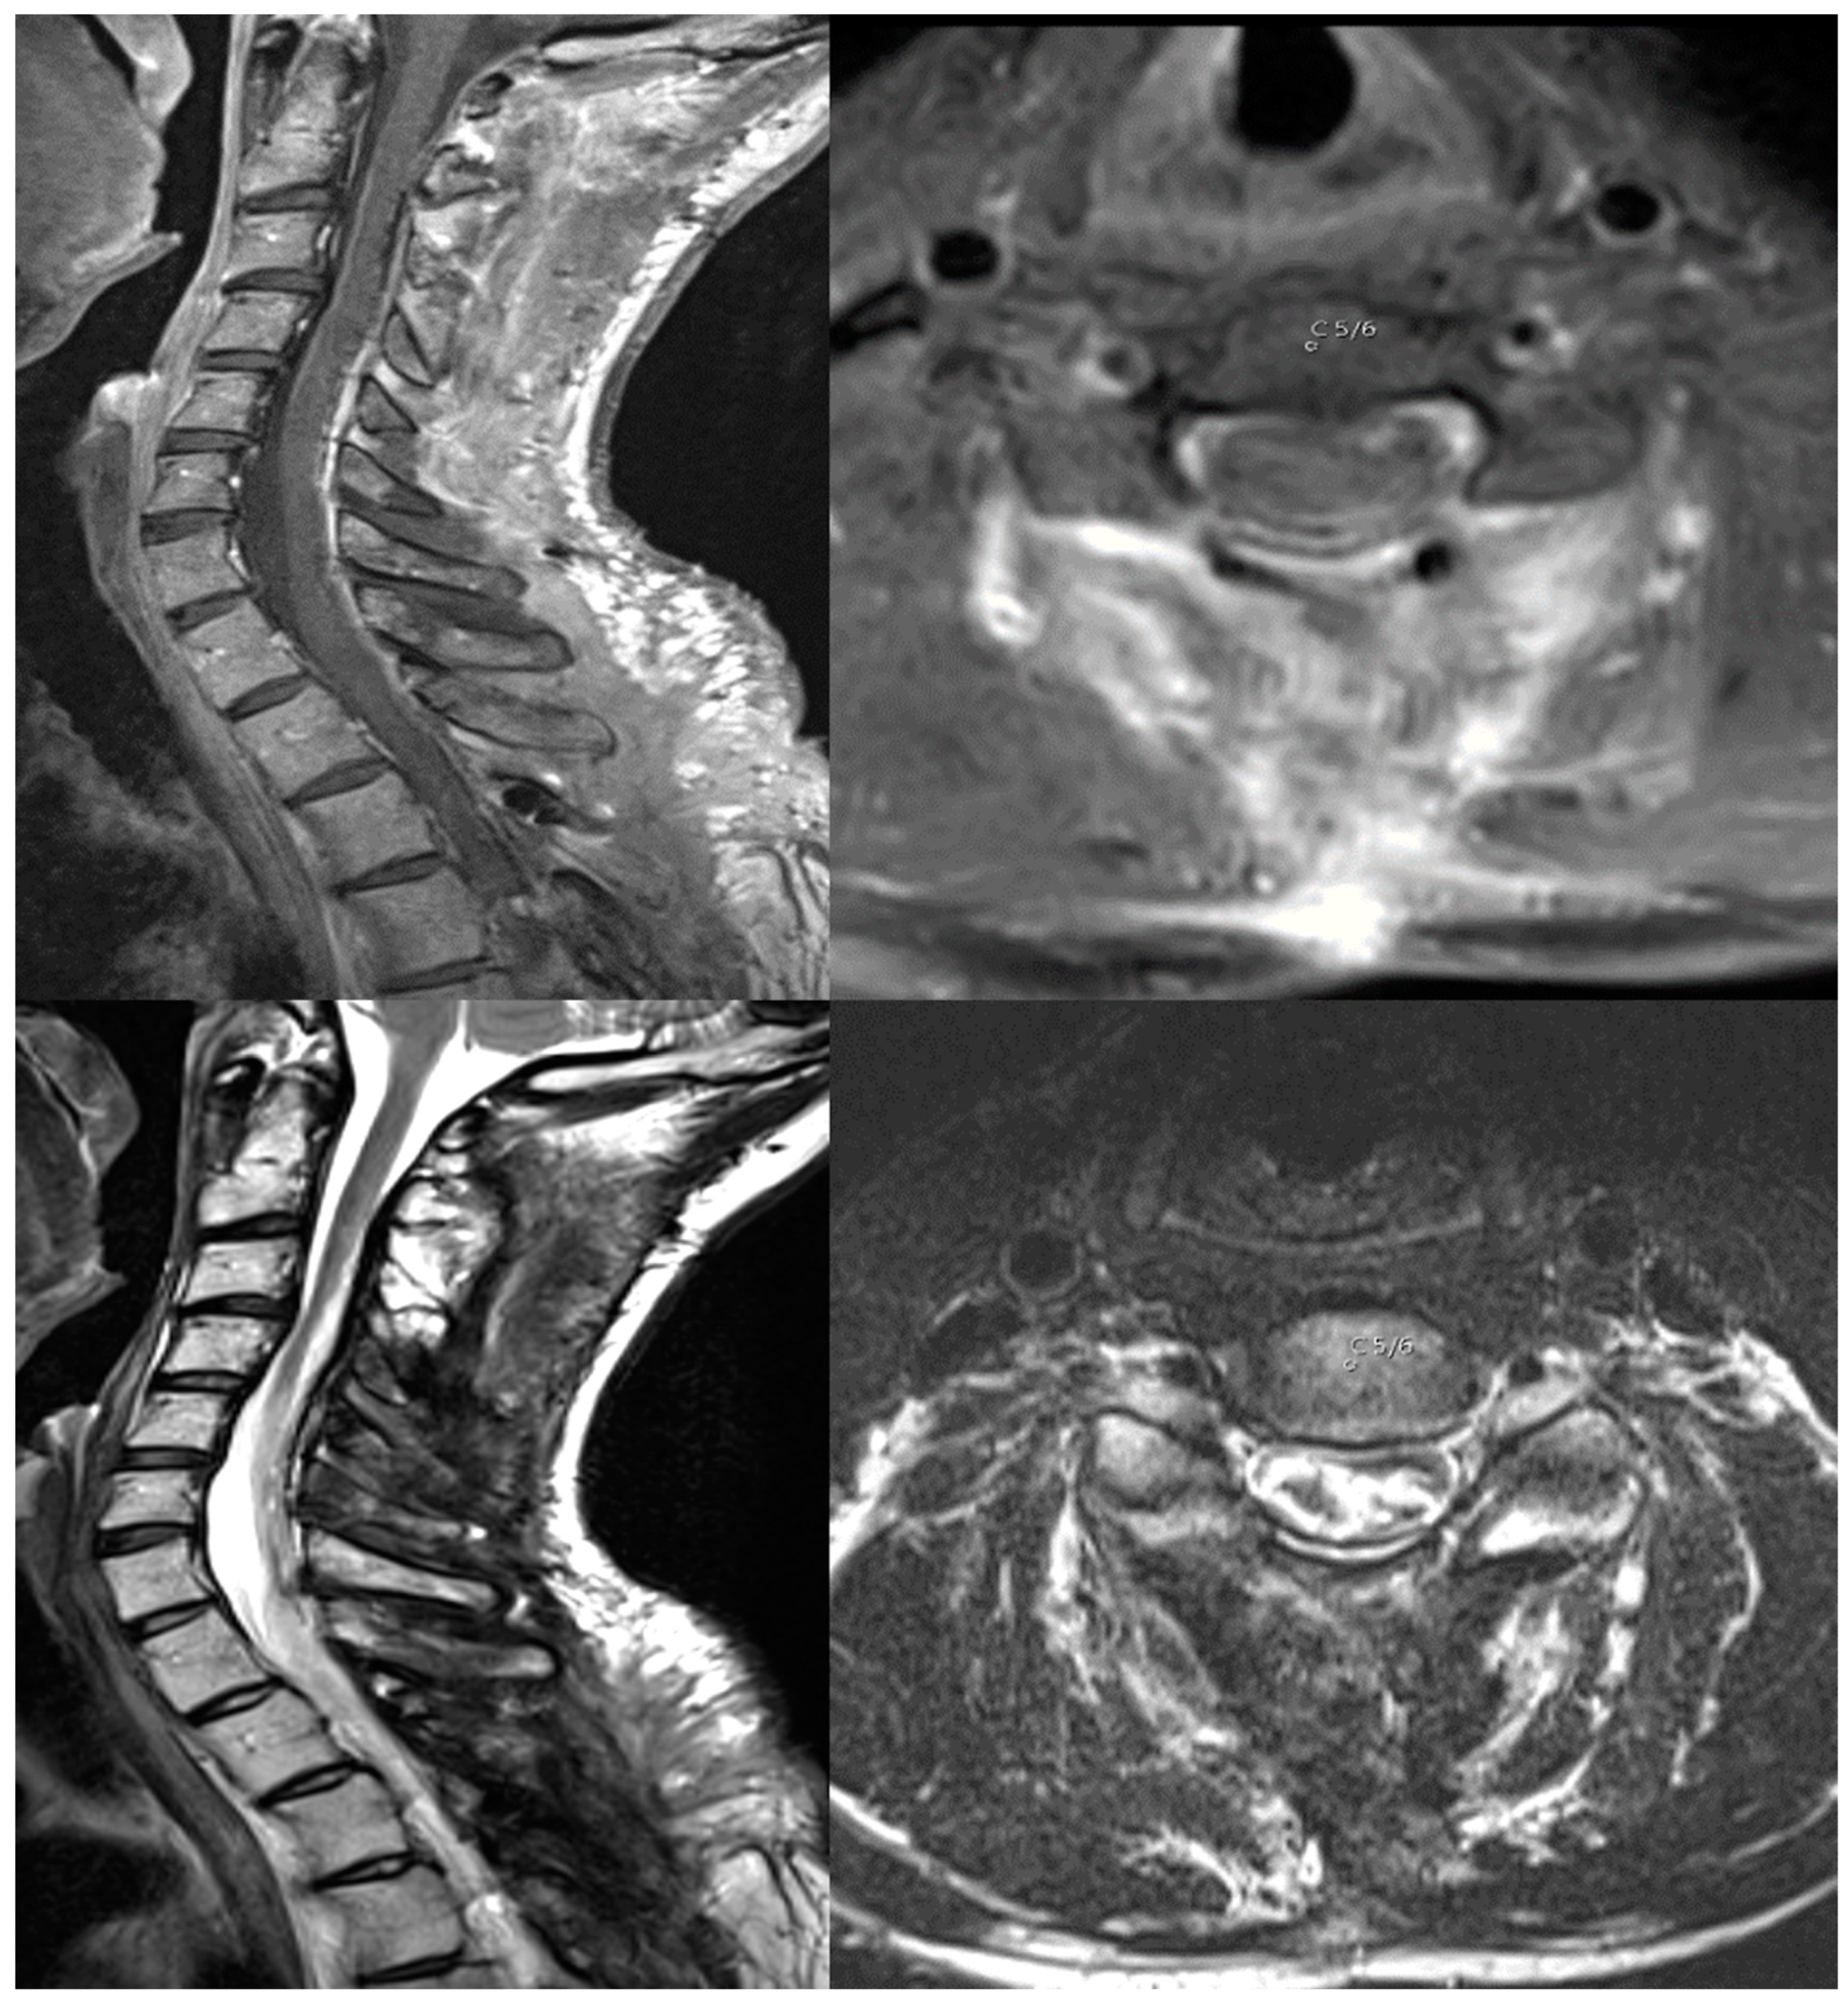

The lesion was resected via laminoplasties, reaching C2 to Th3 under stable IONM (Figure 2) two weeks later. Histopathology revealed a subependymoma–ependymoma mixed tumor, WHO Grade II. After surgery, the patient suffered from a transient neurological deterioration with a finger flexor paresis 2/5 left and impairment in bladder voiding, requiring catheterization for seven days. Additionally, there was a left-sided hemi-hypesthesia, and the already known 4/5 left leg paresis remained. Nevertheless, the patient subjectively reported significant improvement one week after surgery in comparison to before. There were no complications after surgery, such as hematoma or CSF leakage. Three months after discharge, the patient received radiation therapy for 1.5 months, reaching from C1 to Th4, including the spinal canal, due to small residues of stroma on the dura. The total dosage was 50.4 Gy with five fractions of 1.8 Gy each week. After radiotherapy, the left-sided hemi-hypesthesia and 4/5 leg paresis remained. The patient maintained his neurological functionality with a Grade II mMS. After radiation, there were no signs of a tumor recurrence in the MRI scans after 6 months of follow-up. The patient was pain-free upon the follow-up visit.

Figure 2. T1-MRI scan with contrast enhancement (upper image) and T2-MRI scan (lower image) showing the gross total resection of the tumor. The axial images depict level C5/6.